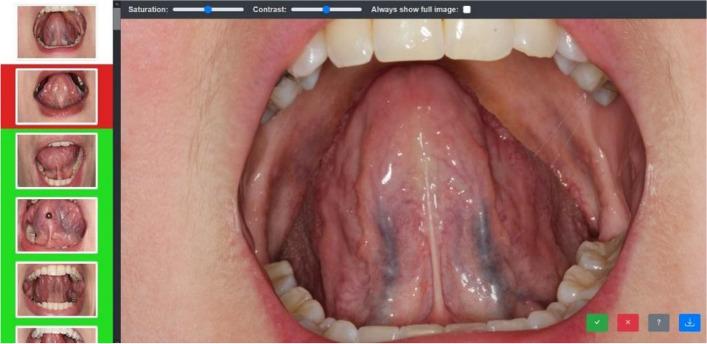

In a diagnostic study, the clinical inspection of 78 patients by 23 clinicians was examined for the diagnosis of SV. Digital images of the underside of the tongue were taken from each patient. The physicians were then asked to rate them for the presence of sublingual varices (0/1) in an online inspection experiment. Statistical analysis for inter-item and inter-rater reliability was performed in a τ-equivalent measurement model with Cronbach's [Formula: see text] and Fleiss κ.

The interrater reliability for sublingual varices was relatively low with κ = 0.397. The internal consistency of image findings for SV was relatively high with α≈ 0.937. This shows that although SV inspection is possible in principle, it has a low reliability R. This means that the inspection finding (0/1) of individual images often cannot be reproduced stably. Therefore, SV inspection is a difficult task of clinical investigation. The reliability R of SV inspection also limits the maximum linear correlation [Formula: see text] of SV with an arbitrary other parameter Y. The reliability of SV inspection R = 0.847 limits the maximum correlation to [Formula: see text] (SV, Y) = 0,920-a 100% correlation was a priori not achievable in our sample. To overcome the problem of low reliability in SV inspection, we propose the RA (relative area) score as a continuous classification system for SV, which normalises the area of visible sublingual veins to the square of the length of the tongue, providing a dimensionless measure of SV.